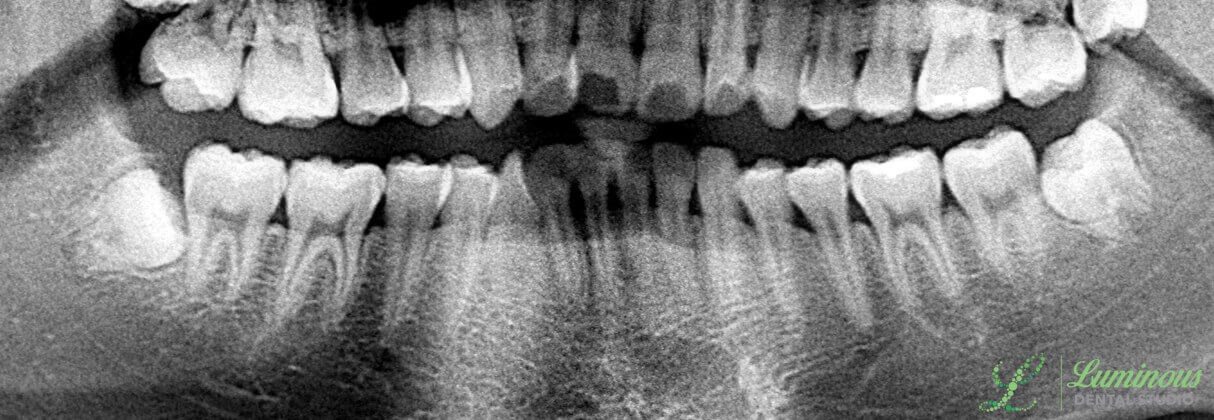

Your wisdom teeth (third molars) can cause some serious problems and damage to your overall dental health if you need to have them removed. Luminous Dental Studio offers nonsurgical and surgical wisdom teeth extractions with our experienced general dentists, Dr. Minho Chang and Dr. Nam Kim. When it is time to make the decision on how to take out the wisdom teeth, you can rely on our Luminous Dental Studio dentists to provide you with state-of-the-art technologies to diagnose the problem and to design a strategy that has your best interest at heart. We will capture your wisdom teeth in digital x-rays to check for signs of infection, what they are doing to the surrounding teeth and gums, and whether or not a bone will have to be removed to get an impacted wisdom tooth out. Our Luminous Dental Studio dentists, Dr. Chang and Dr. Kim, can extract troublesome teeth quickly and comfortably. Book your appointment to discuss tooth extractions.

Older children and young adults are the usual candidates for the removal of their wisdom teeth. The type of extraction you have is based on the health of each tooth. Some patients will qualify for a nonsurgical extraction (or traditional extraction) for removal. Candidates for the surgical removal of a wisdom tooth may already be experiencing dental problems, such as impaction, overcrowding, an infection, and more. There are several indications of an impacted tooth that will tell Dr. Kim or Dr. Chang how to proceed with the removal. If you do not have an impaction, you would make an ideal candidate for nonsurgical extraction. In the event that you have impacted third molars (even if they have not erupted out of the gumline), a surgical approach may be necessary.